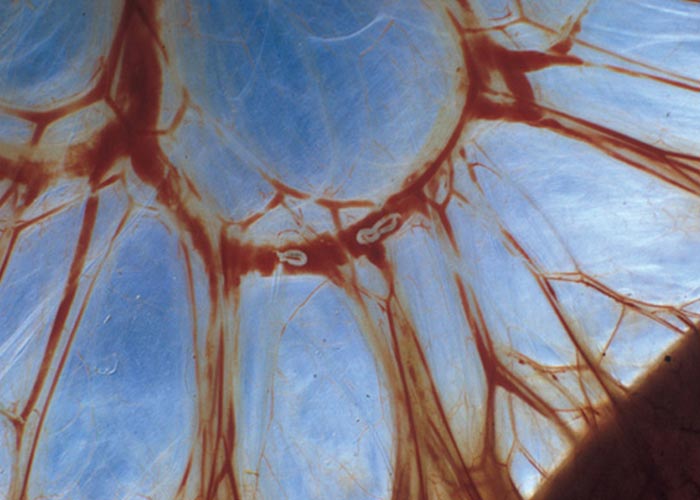

Muellerius capillaris is a heteroxenous parasite or 'biohelminth' that uses snails and slugs as intermediate hosts. The eggs develop in the lungs of the host and the first stage larvae pass out with the faeces. The tail of the larva has a spine and an undulating tip. These larvae can resist a fair amount of desiccation, are not killed by freezing, and are most active at temperatures of about 17-27 °C. For further development, they must enter a mollusc –the intermediate host –by penetrating the foot of the mollusc. The infective stage (L3) is reached after 12 to 14 days. These larvae can live in the snail/slug for as long as it lives –and for a week after its death. The final host becomes infected when it consumes the mollusc with its food. Larvae pass through the intestinal wall into the mesenteric lymph nodes, where they moult to the fourth stage. They then go to the lungs via the lymph and blood vessels. Trans-placental transmission takes place and larvae have been found in the liver and lungs of foetuses and new-born lambs. The pre-patent period is 6 to 10 weeks. The life cycle of Mammomonogamus is unknown.